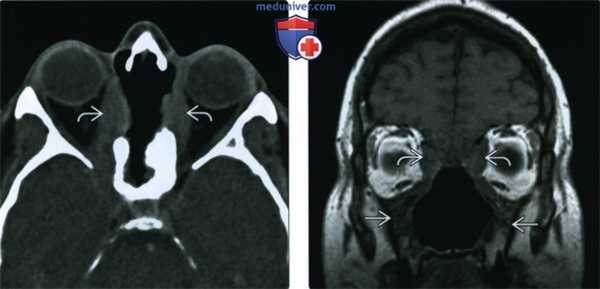

(Слева) При аксиальной КТ без КУ определяется деструкция верхней части носовой перегородки и глазничной пластинки с обеих сторон. В этом случае имеет место гранулематоз с распространением в обе орбиты.

(Справа) При корональной МРТ Т1ВИ у этого же пациента определяется нарушение нормальной анатомии носа и утолщение стенок верхнечелюстных пазух. Жировые пластинки между измененными мягкими тканями и внутренней прямой и верхней косой мышцами видны неотчетливо.

3. МРТ носа, пазух при гранулематозе Вегенера с полиангиитом:

• Т1ВИ:

о Узловые образования с низким или промежуточным сигналом

• Т2ВИ:

о Узлы с ↓ сигналом (в сравнении с воспаленной слизистой оболочкой = ↑ Т2)

о Отек мягких тканей с ↑ сигналом при обострении с распространением в соседние мягкие ткани

• Т1 ВИ С+:

о Контрастирующиеся мягкотканные узлы и опухолевидные образования в слизистой оболочке

о Поражение орбиты: контрастирующееся инфильтративное образование в орбите, часто связанное с процессом в носу/ пазухах

о Утолщение оболочек мозга и их контрастное усиление